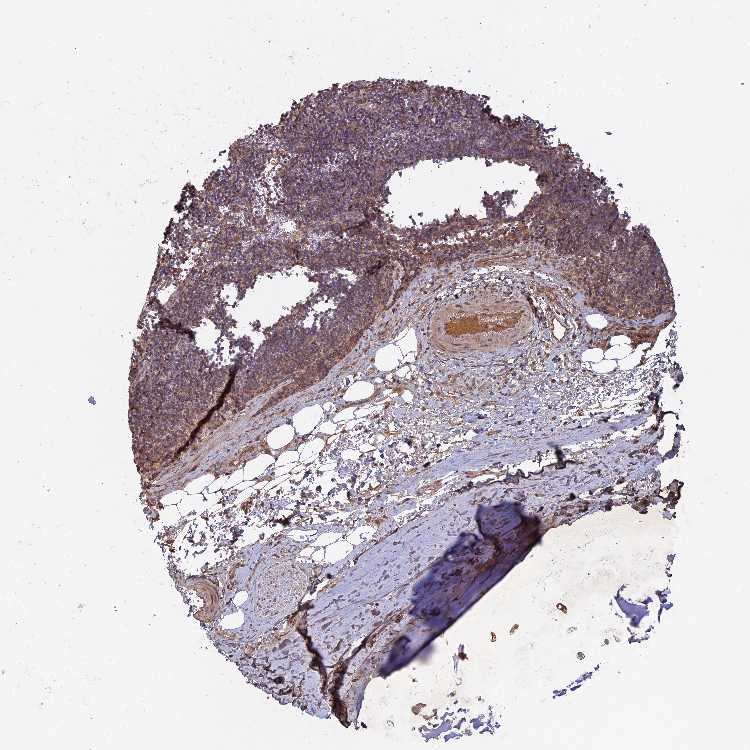

SOFT TISSUE 1 - Antibody stainingi

Antibody staining in the annotated cell types in the current human tissue is reported as not detected, low, medium, or high, based on conventional immunohistochemistry profiling in selected tissues. This score is based on the combination of the staining intensity and fraction of stained cells.

Each image is clickable and will lead to virtual microscopy that enables deeper exploration of all samples and also displays staining intensity scores, fraction scores and subcellular localization as well as patient and tissue information for each sample.

Antibody HPA041994

Chondrocytes Medium

Fibroblasts Medium

Peripheral nerve Low